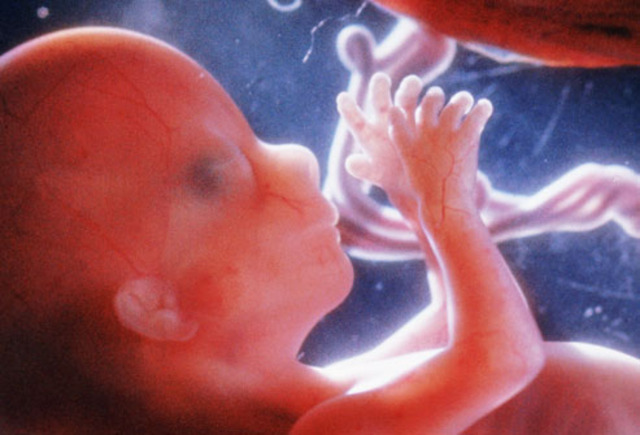

• Month 4 Baby

Month 4 Baby

Size: about 3 inches (7.6 cm) long, 1 ounces (28 g) as month begins.

Can suck it's thumb, sallow, hiccup, and move around.

Facial features become clearer.